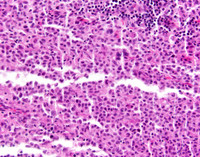

Indeterminate dendritic cell tumor-CD1a

Category: Macrophage/Histiocytic and dendritic cell Neoplasms and disorders (2015) > L group > Indeterminate cell histiocytosis